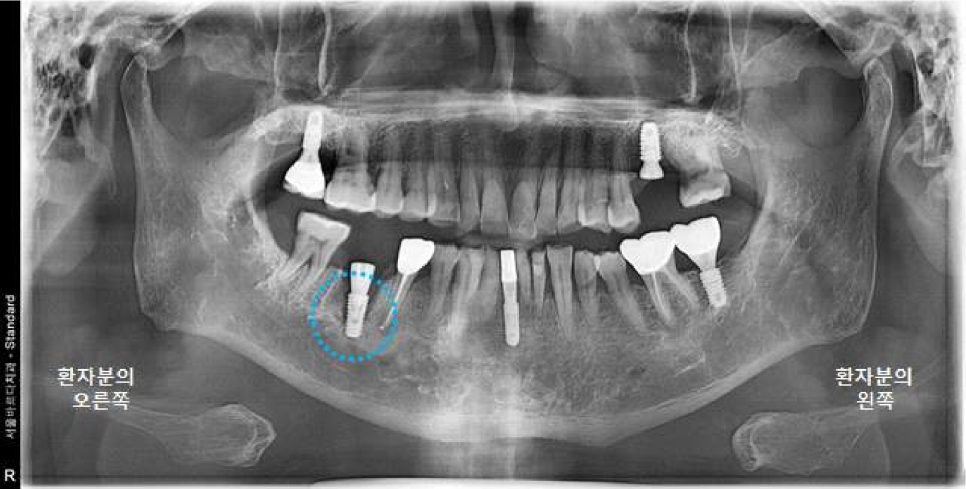

완료된 파노라마 엑스레이 사진입니다!

왼쪽 오른쪽 교합도 잘 맞으니 부드러운 음식부터 식사 잘 시작해보시고,

불편사항 생기시면 미리 전화 주시고 내원하시기로 하셨습니다.